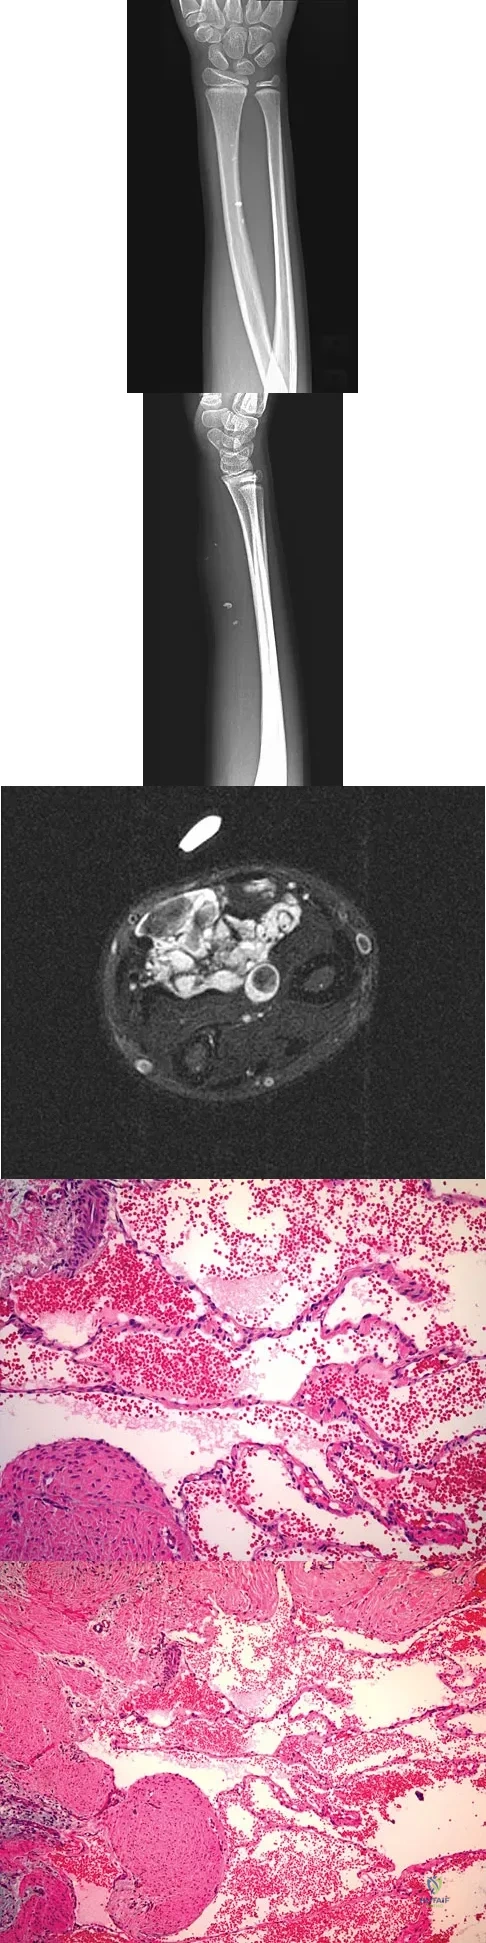

A 7-year-old girl has had a painful forearm for the past 2 months. Examination reveals fullness on the volar aspect of the forearm. Radiographs and an MRI scan are shown in Figures 42a through 42c. Biopsy specimens are shown in Figures 42d and 42e. What is the most likely diagnosis?

Explanation